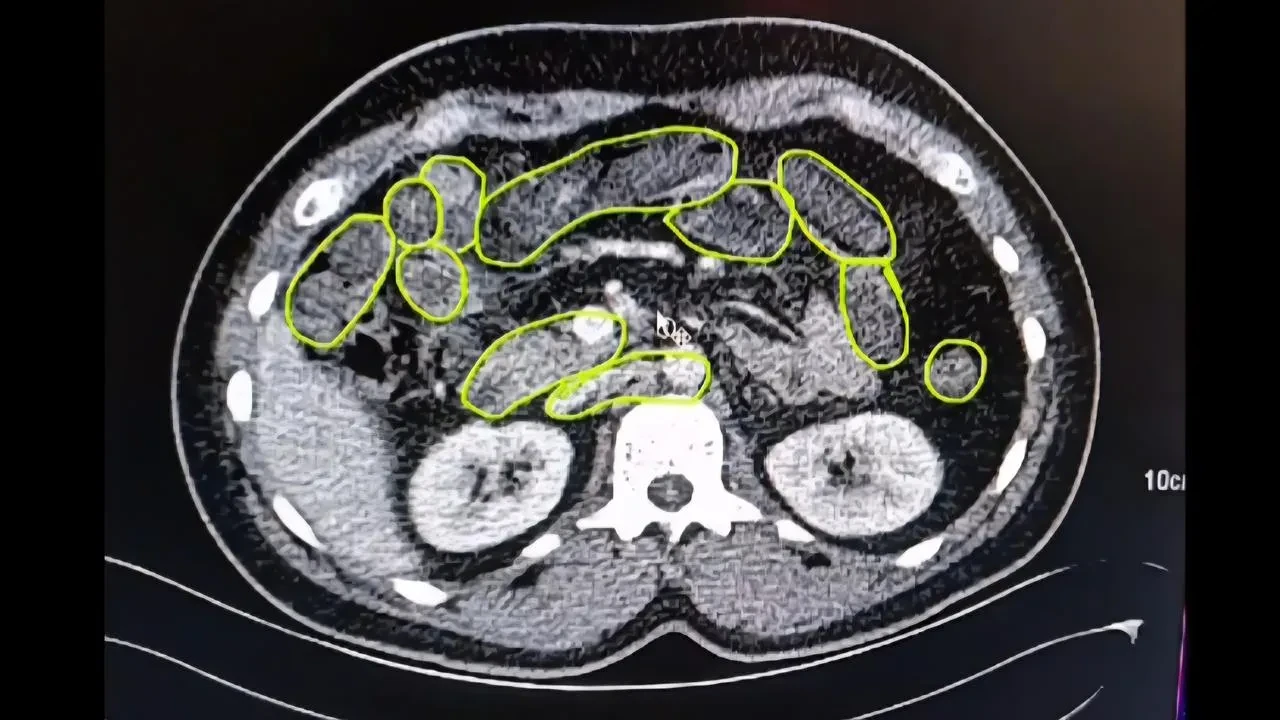

Kayseri'de jandarma ekipleri, mide ve bağırsaklarında uyuşturucu madde taşıyan 3 yabancı uyruklu şüpheliyi yakaladı.

İl Jandarma Komutanlığı, İran'dan uyuşturucu getiren şahısları takip altına aldı. Ankara yolunda durdurulan araçta ilk aramada 20 gram uyuşturucu ele geçirildi.

Hastanede Detaylı İnceleme

Şüpheliler Kayseri Şehir Hastanesinde iç beden muayenesine alındı. Yapılan kontrolde mide ve bağırsaklarında çok sayıda kapsül tespit edildi.